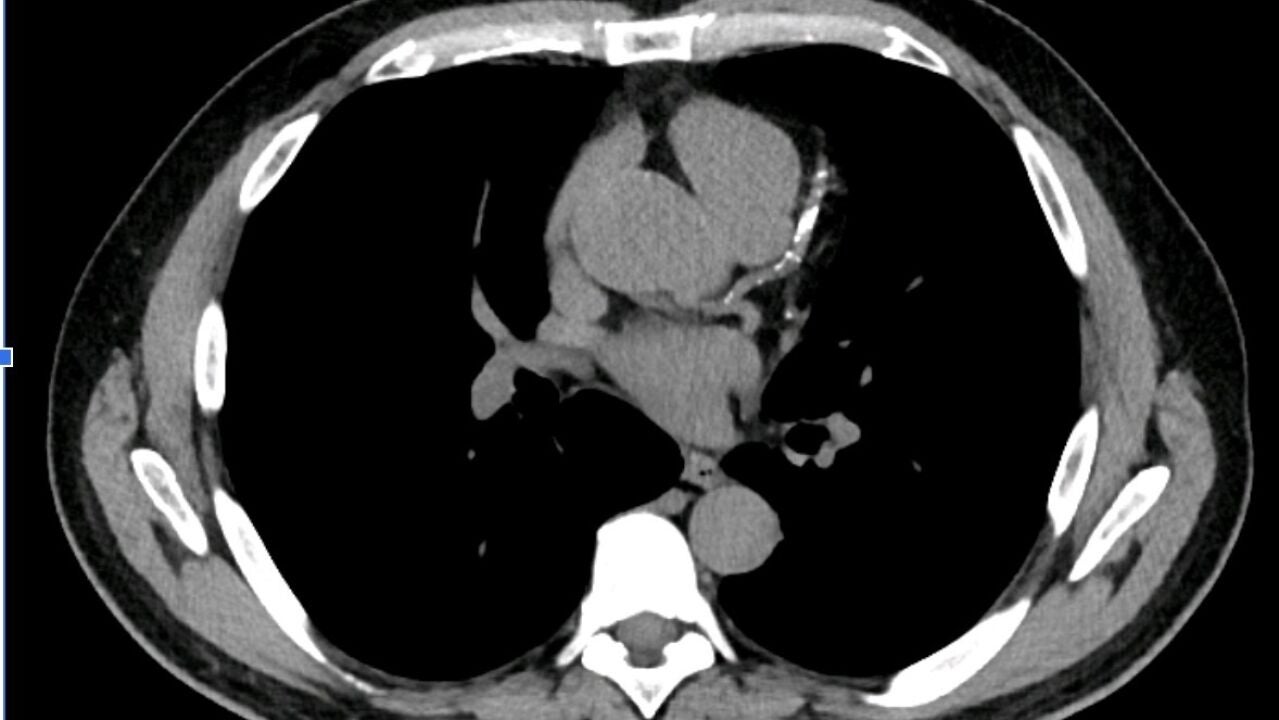

Niveles elevados de esta proteína se asocian a una riesgo 40% mayor de sufrir arterosclerosis coronaria multivaso, una condición que se relaciona con la posibilidad de padecer un evento cardiovascular...